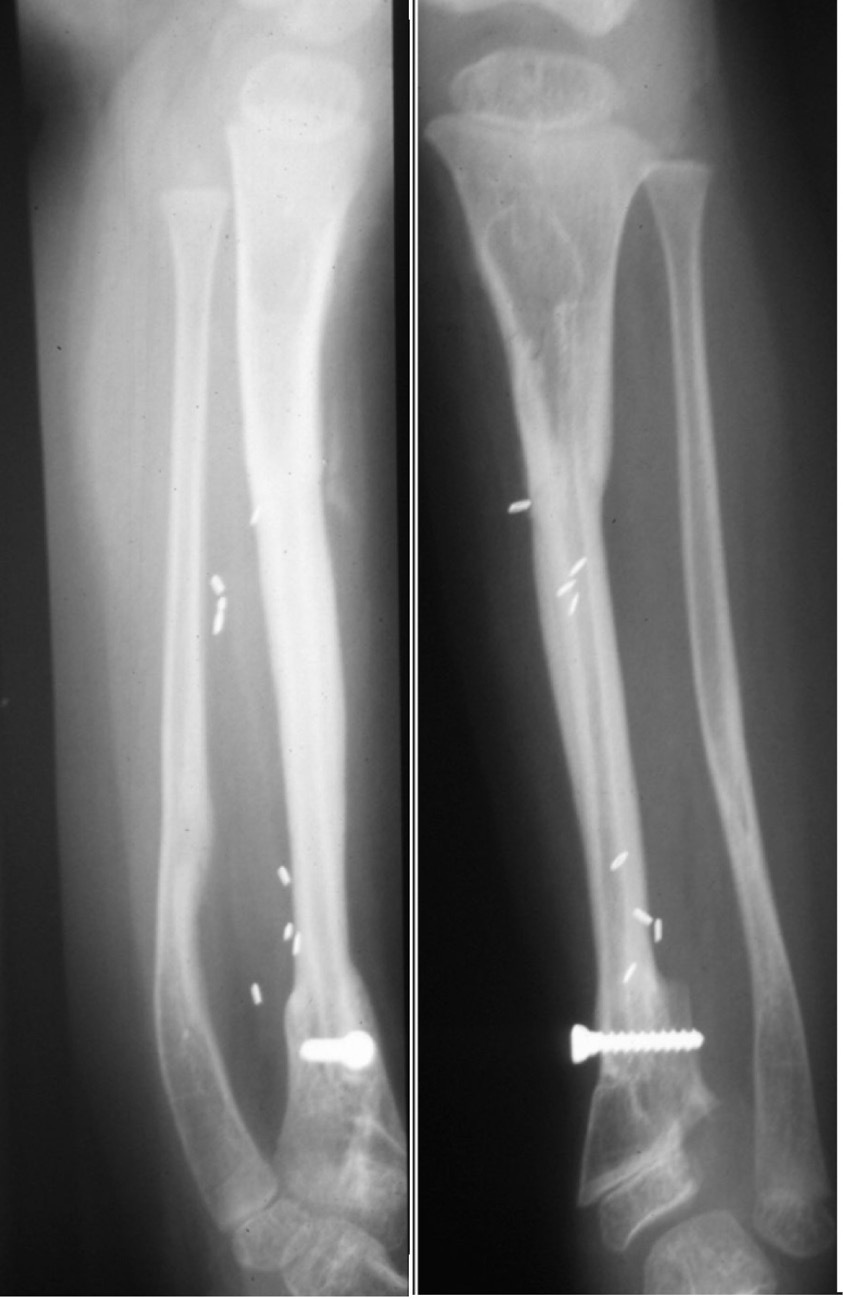

Another form of fixation is an intramedullary nail or rod used in two of our nine cases of resection of a pseudarthrosis of the tibia in a child shown in Cases 12 and 13 (Figures 32 and 33). In these two cases, the distal tibial fragment could not be fixed to the fibula with a screw. Instead a Rush nail was passed from below through the heel, calcaneum, talus and distal tibia and into the medullary cavity of the transplanted fibula. The result was exactly the same as the other seven cases. Even in plaster you can’t keep a child still! By six weeks all, including the two with nails, showed union and early bone hypertrophy (Figures 32 and 33).

The importance of centralising the fibula within the medullary cavity of the femur or tibia is again reinforced by another case done at the Royal Melbourne Hospital. The fibula was used to reconstruct the femur but fixed rigidly with a plate and screws in Case 14 (Figure 34A). Twelve months later there was union but no sign of hypertrophy of the transplant. Then the plate broke. A Kuntscher nail was inserted from above and down through the medullary cavity of the fibula. It shattered forming a row of ‘bangles’ around the nail (Figure 34B). Two years later, having walked on his ‘box of bones skewered by the K-nail,’ he was located and the leg radiographed. Except for one level, there was union and hypertrophy of all bone bangles (Figure 34C).